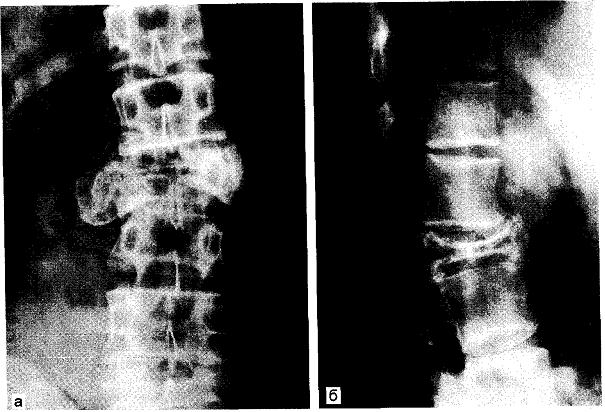

Аневризмальная киста II поясничного позвонка (рентгенограмма)